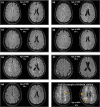

Results: Seven cases were identified that fulfilled the mSVDNOTCH3 criteria, with a mean age of 56.6 years (range, 50-72). All of these individuals harbored a NOTCH3 variant located in one of EGFr domains 7-34 and had a normal brain magnetic resonance imaging, except the oldest individual, aged 72, who had beginning confluence of WMH (Fazekas score 2) and 1 cerebral microbleed. mSVDNOTCH3 cases had very low levels of NOTCH3ECD aggregation in skin vasculature, which was significantly less than in symptomatic EGFr 7-34 CADASIL patients (P=0.01). Six mSVDNOTCH3 cases had absence of granular osmiophilic material deposits.